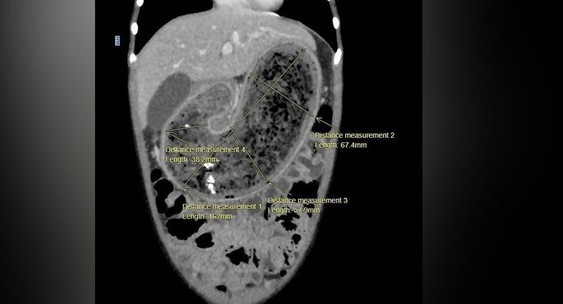

Проведенная компьютерная томография подтвердила наличие огромного трихобезоара, который полностью заполнил желудок, двенадцатиперстную кишку и начальный отдел тонкой кишки.Москва 24